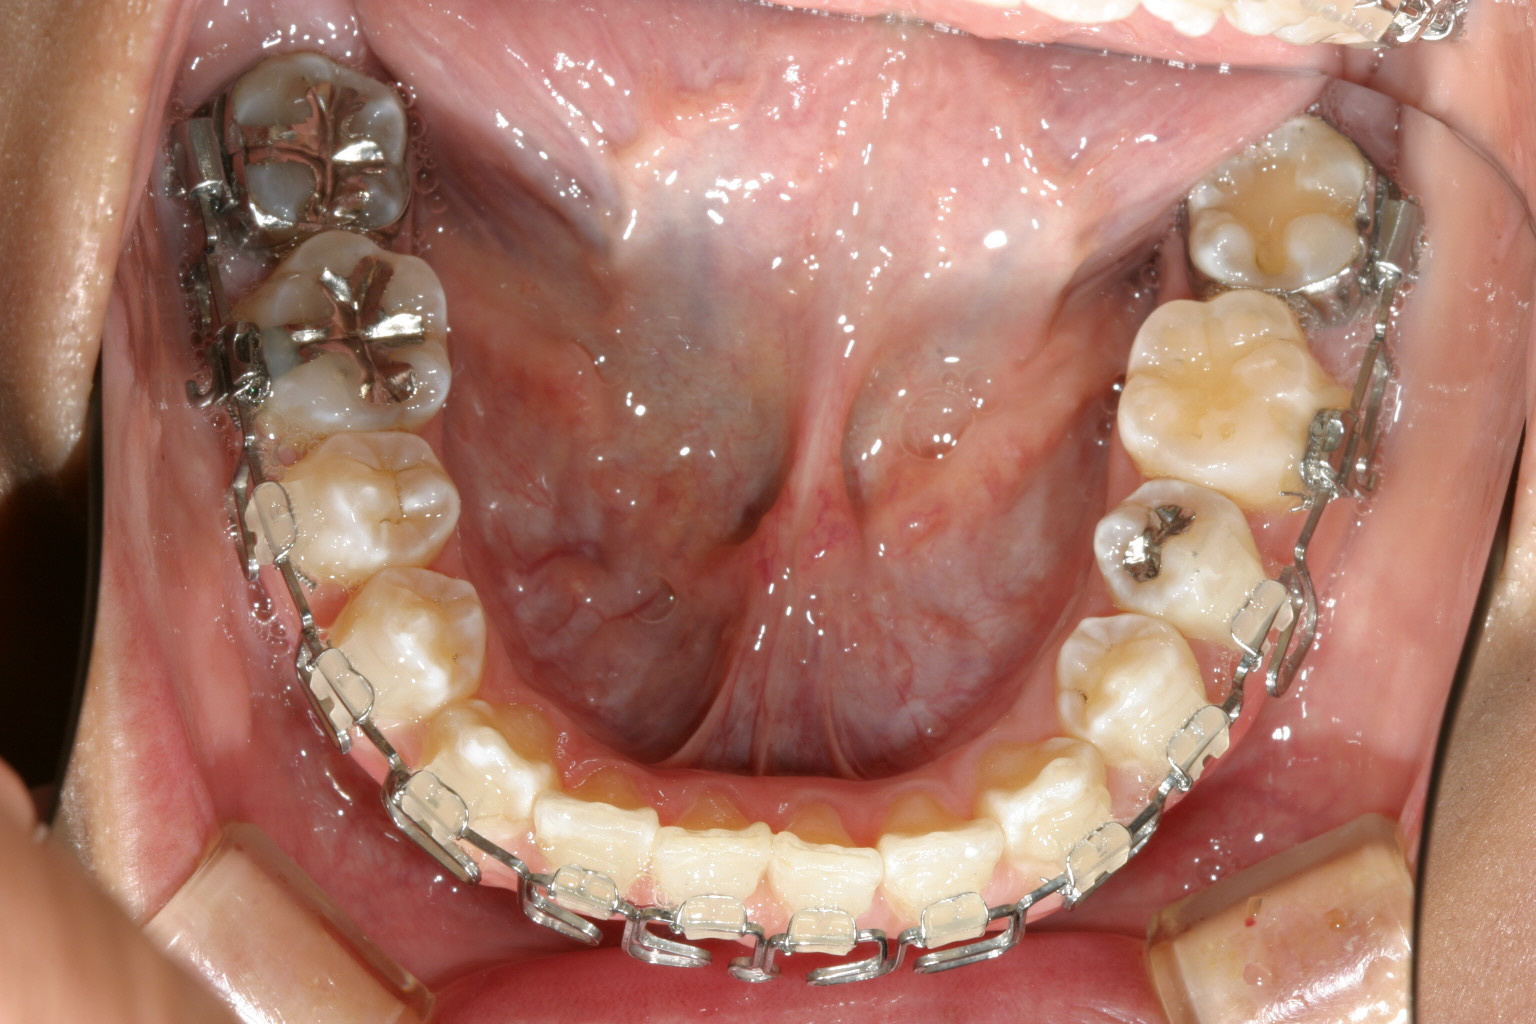

下顎前歯が翼状捻転しています。

下顎もマルチループワイヤーしています。